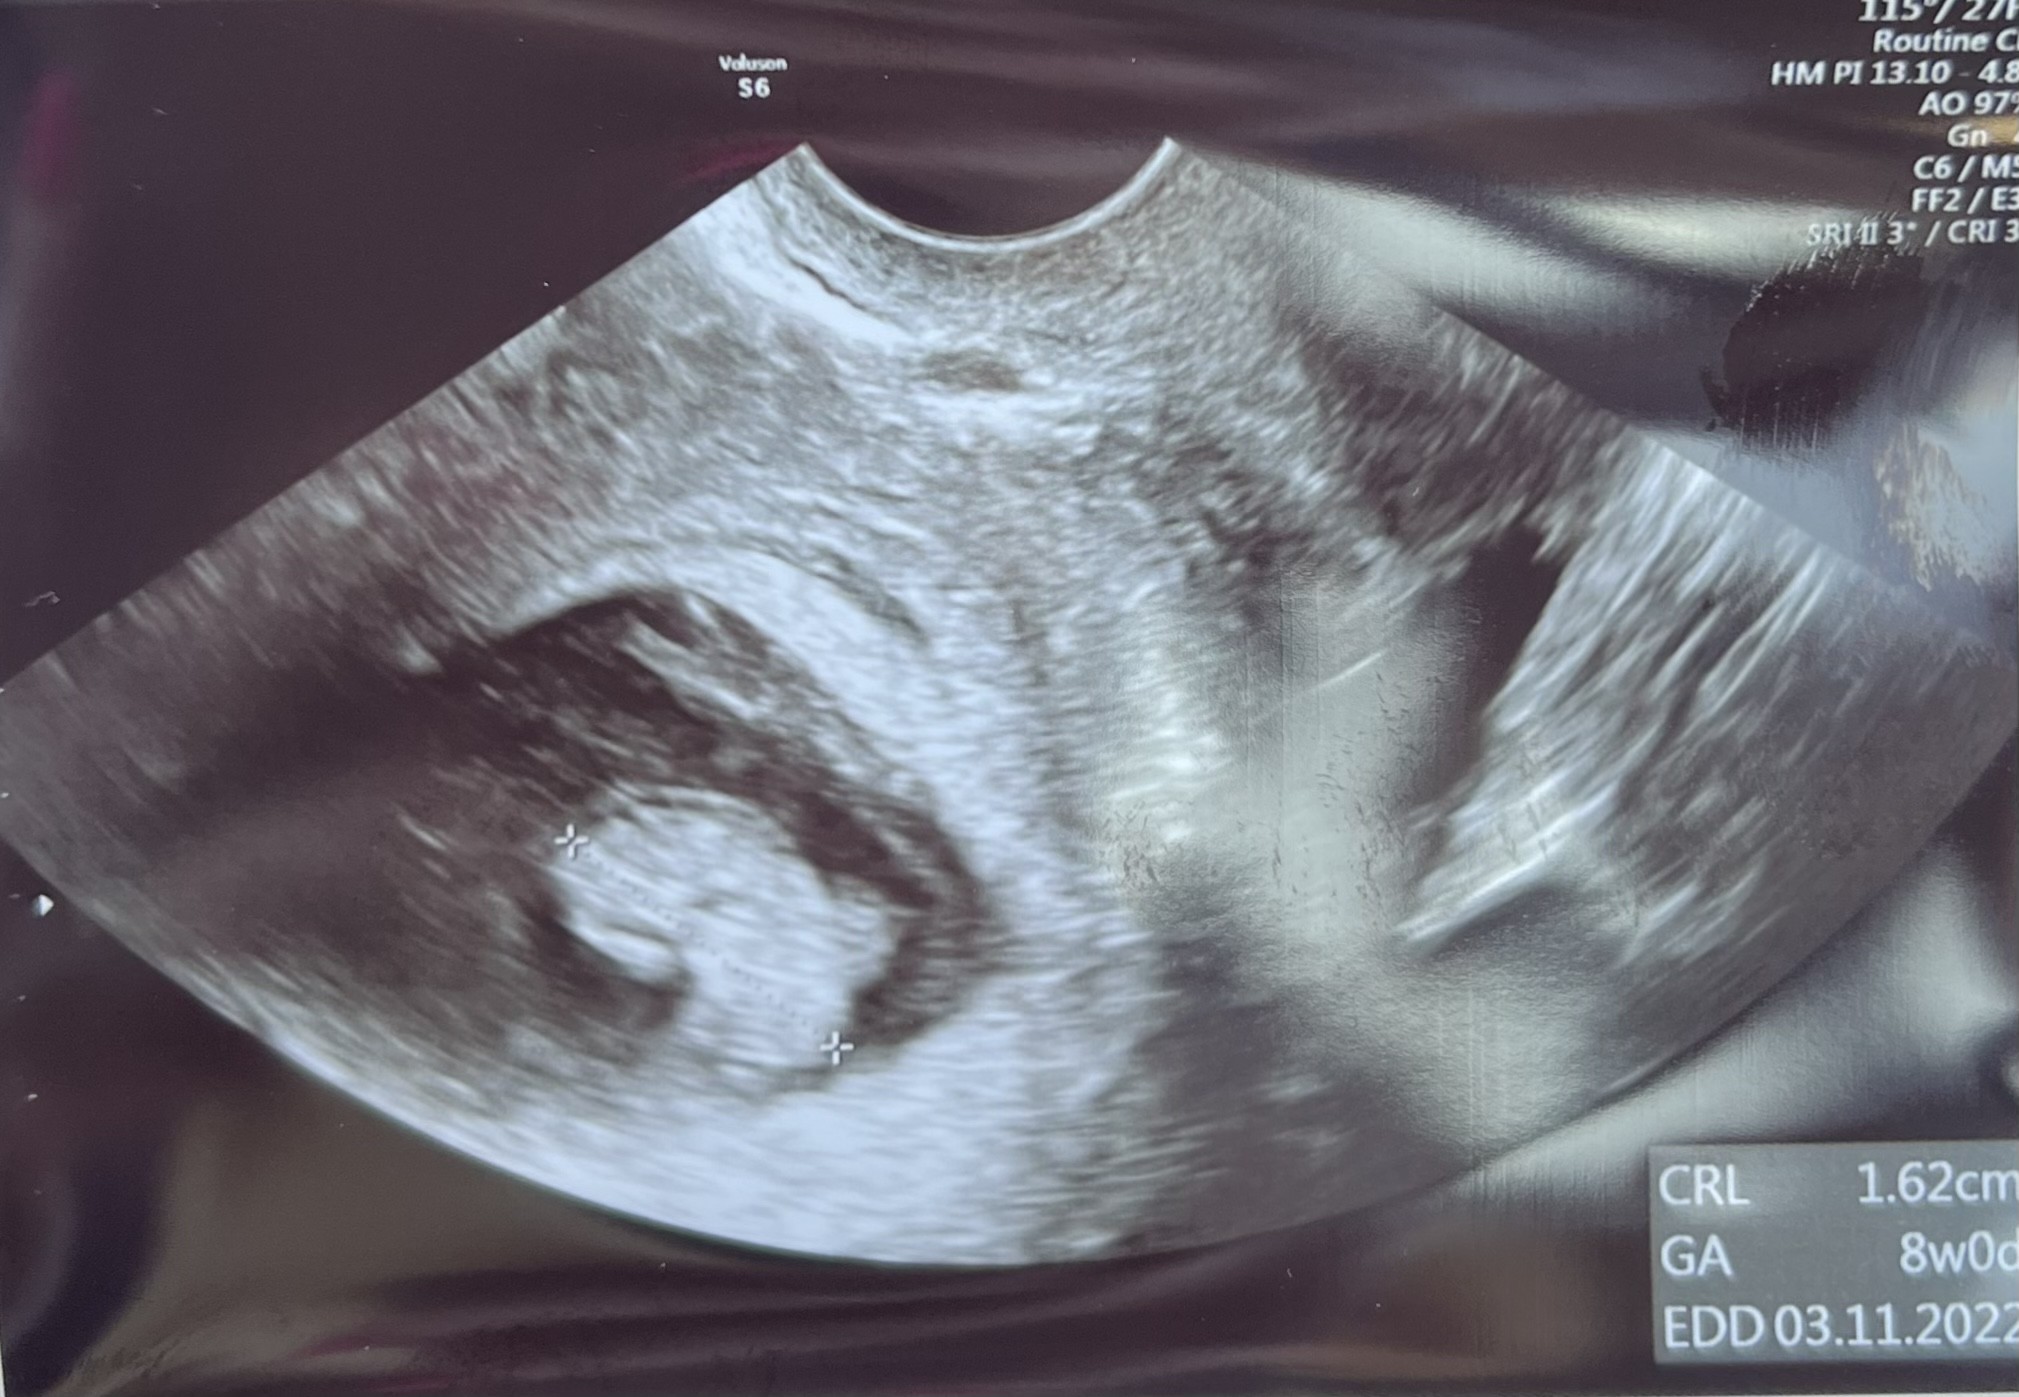

W czwartek bylam na drugiej wizycie u gina, chcialam Wam sie pochwalic moja 8 tygodniowa fasolka a tu sie okazalo, ze mam 85 stron do nadrobienia

ale udalo sie i w koncu nadszedl ten moment. Przedstawiam Wam moja fasoline

W czwartek bylam na drugiej wizycie u gina, chcialam Wam sie pochwalic moja 8 tygodniowa fasolka a tu sie okazalo, ze mam 85 stron do nadrobieniaale udalo sie i w koncu nadszedl ten moment. Przedstawiam Wam moja fasoline